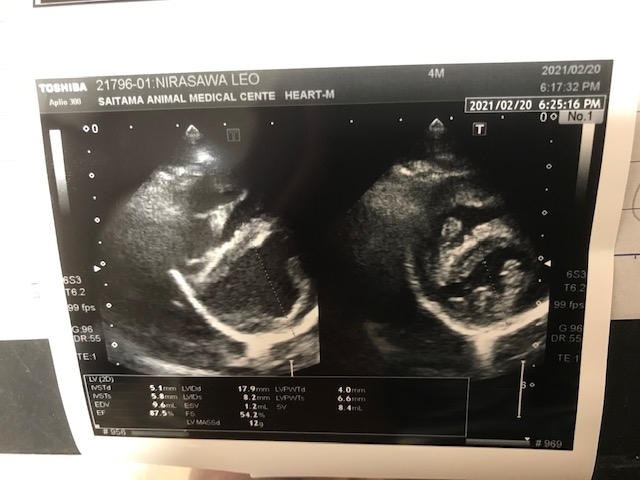

3cmの心臓に対し5.7ミリの穴が空いており(2021.3)心室中隔欠損症と言います。

Leoの心臓は(2021年3月)3センチの心臓に対し5.7ミリの穴が開いており『心室中隔欠損症』と病名はなります。2箇所の疾患があるので、負担が多く、特に麻酔のリスクがあります旨もお話し下さいました。又、動脈管は、とても細く心室中隔欠損症ある為、リスクがとても高い手術になります事も付け加え話して下さいました。

●3cmの心臓に約5.7㍉の穴が開いています。(2021年2月時点)